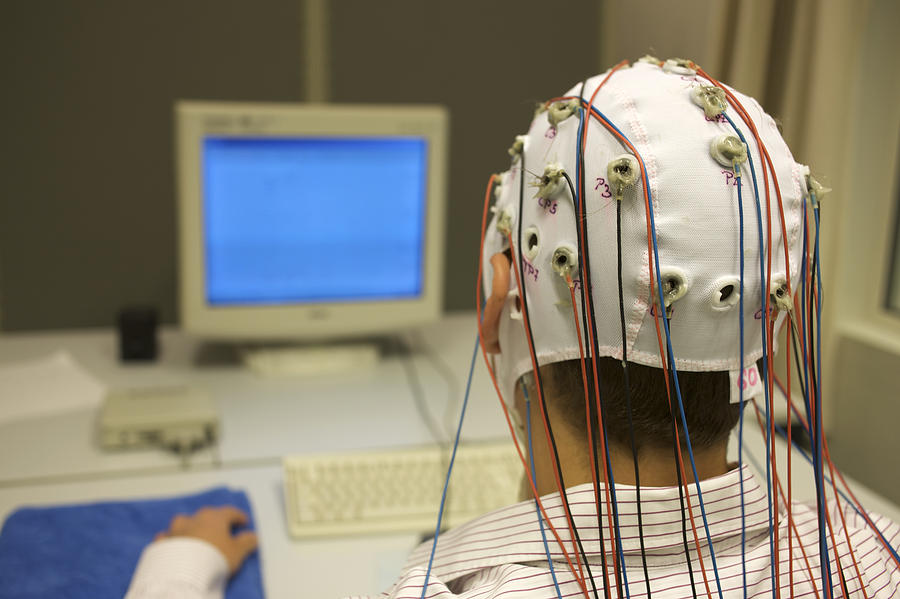

Epilepsy/ फिट्स निदान कसं होत?

Epilepsy/ फिट्स यामध्ये तज्ञ डॉक्टर तुम्हाला ईईजी,रक्त तपासण्या,MRI किंवा CT Scan सारख्या टेस्ट करायला लाऊ शकतात. सोबत काही फिजिकल टेस्ट करून सुद्धा ह्याची तपासणी केली जाऊ शकते.